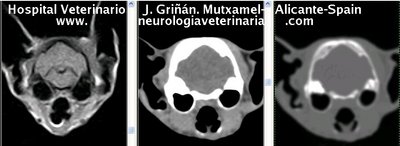

Se muestran cortes transversales de Resonancia Magnética (imagen a la izqda del lector), TC contrastado para tejidos blandos (imagen del centro) y TC contrastado para tejidos duros (imagen de la derecha del lector).

Nótese como la Resonancia supera al TC en el contraste de tejidos blandos (encéfalo y médula espinal) y en el de líquidos (ojo y líquido cefalorraquídeo), mientras que el TC supera a la resonancia en el contraste de tejidos duros (hueso) y aire (senos, cavidad nasal y bullas)

Cortes a nivel de los lóbulos cerebrales frontales